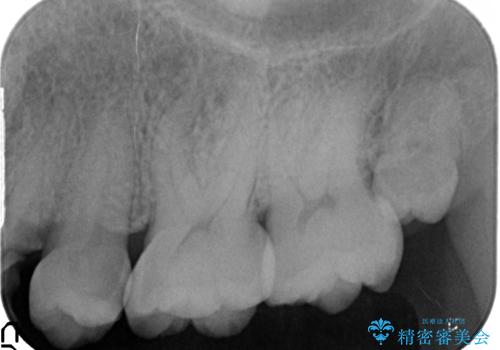

- 虫歯が深かったため、根管治療を行い、土台を立て直しかぶせ物を製作します。

虫歯で奥歯が真っ黒になり崩壊していましたが、悪い部分を完全に取り除き、丁寧に修復することでまた長く機能させることができます。